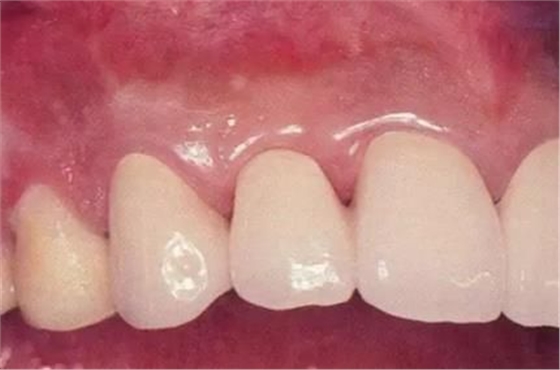

▲圖17-9

佩戴最終修復(fù)體時。

橋體部牙齦看上去更加自然。